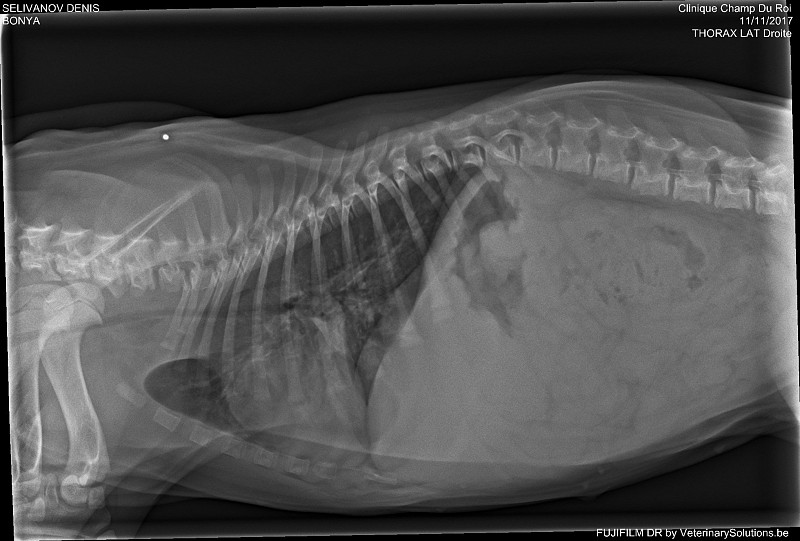

Коллапс трахеи форум

Коллапс трахеи форум 116 фотографий